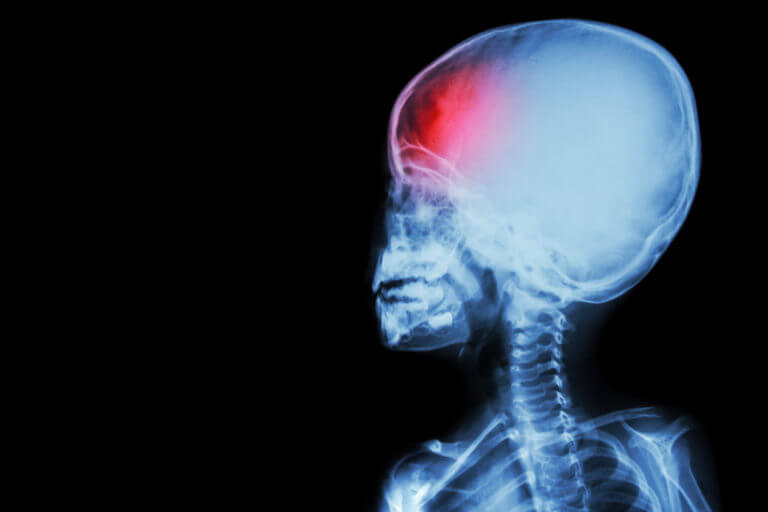

Pediatric seizures are not just due to problems with the brain’s structure but can also be a complication of stroke, traumatic brain injuries like concussions, and brain tumors. Treatment is provided by a neurologist, a doctor who specializes in neurological conditions.